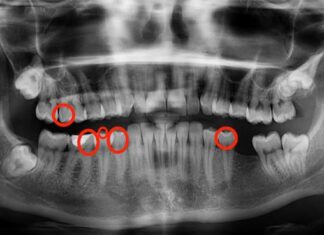

- Mundgesundheit: Zahnpasten, die Backpulver enthalten, verbessern nachweislich die Plaqueentfernung und die Zahnfleischgesundheit, wahrscheinlich aufgrund ihrer milden säureneutralisierenden Eigenschaften.